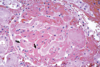

Pale foci subserosally

漿膜下蒼白小點- 發生在肝臟

- 因腹腔內壓(intraabdominal pressure)上升,將血液擠壓出去

- bacterial action:細菌將組織降解,切片下沒有細胞核像凝固樣壞死(coagulation necrosis),沒有炎症反應且出現很多細菌,可判斷為死後變化

- 外觀:使肝臟表面上出現白色小點區域,變得不圓滑